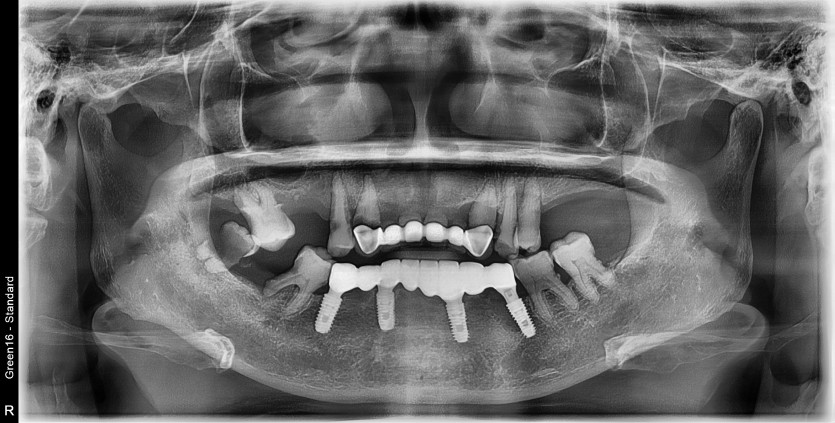

상악 전체 임플란트 증례입니다.(하악 일부)

11개의 임플란트로 완성하였습니다.